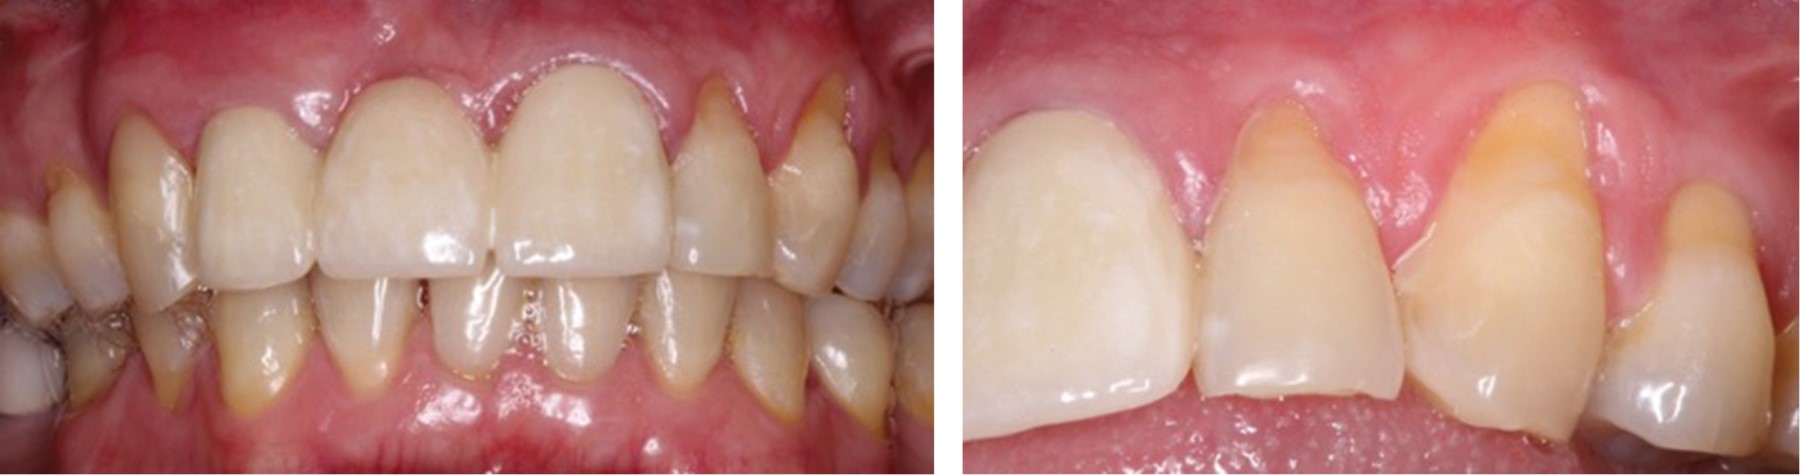

Figure 2